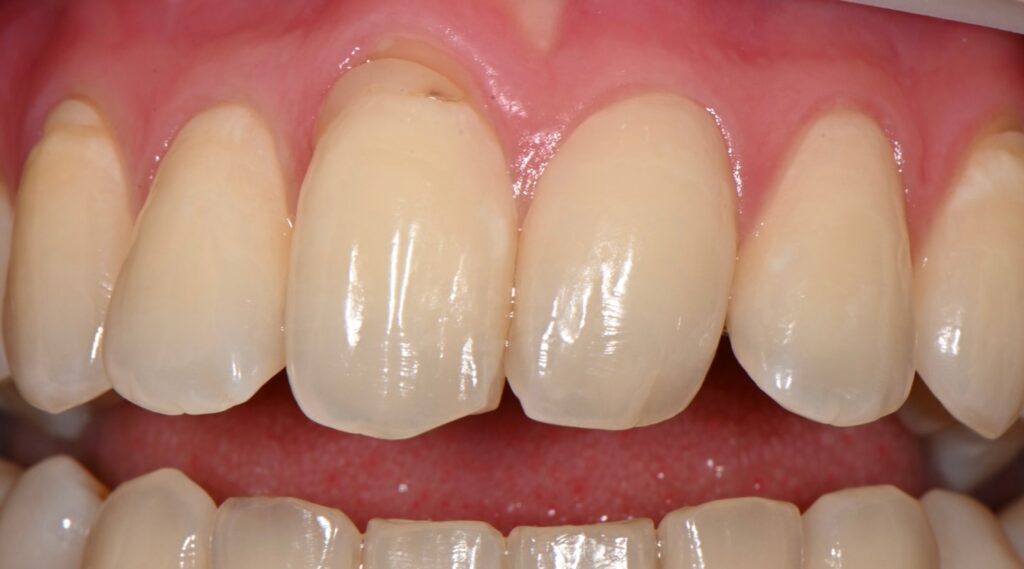

1차 피니싱과 폴리싱 완료후 모습입니다

완전히 자연스러운 모습입니다만

치경부 즉 치아의 경계 부위의 형태가 조금 걸립니다

하지만 이 부분은 러버댐이 잇몸을 눌러서 생긴 현상이기에

2주후 추가 피니싱을 하기로 하였습니다

내원당일의 모습

레진 치아성형은 치료 당일은

1.색상이 발현되지 않아서 달라보일 수 있습니다

2.잇몸이 차오르는 모습을 봐야 합니다

-2주 후 기다려서 추후 경과를 봅니다-